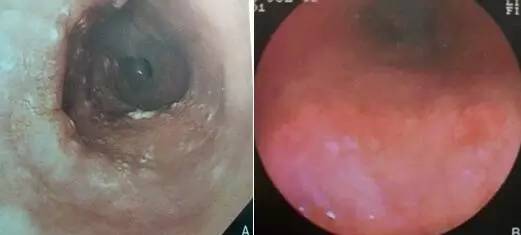

白光内镜下,食管早癌表现并不典型,可以表现为局灶的糜烂、突起、甚至只有颜色的改变,需要检查者仔细观察,防止漏掉病变,对于怀疑的病变,不要怕麻烦,一定要积极进行进一步检查。根据白光内镜下的表现,日本内镜协会将食管早癌分为以下四型:I型-隆起型、II型-平坦型、III型-凹陷性;平坦型又可分为IIa-轻微隆起型、IIb-完全平坦型、IIc-浅凹陷型。对于内镜检查医师来说,II型病变最难观察,退镜时应该更加重视食管粘膜的异常,对于食管表面覆盖的唾液等影响观察的覆盖物应充分冲洗,以免漏诊。

图A为IIa型病变,病变区域表面粗糙隆起于正常食管表面 图B三点钟方向有一斑块状IIb型病变,如不仔细观察或被粘液覆盖,极易漏诊 图C为IIc型病变,略有凹陷,表面粗糙